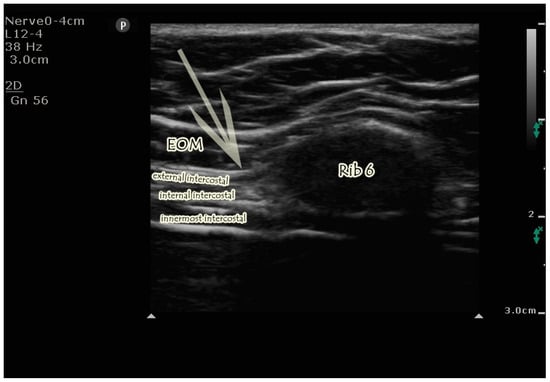

2.4.2. US-Guided EOIB